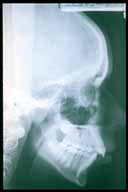

ma la medicina si impossessò presto del nuovo strumento e,

non contenta di osservare ossa, si ingegnò per rendere visibili

anche le parti "molli" del corpo al fine di poter osservare apparato digerente,

fegato, vene e arterie, cervello. Si trattava di rendere opache quelle

zone del corpo per poter essere scrutate dai raggi X. I più anziani

di noi ben ricordano le bevute di bario che si son dovuti fare e pochi,

per nostra fortuna, quelli che ricordano le pericolosissime iniezioni

in vena di liquidi opacizzanti il sangue che, ovviamente, si praticavano

soltanto in casi di estrema necessità.

Oggi con la TAC (la tomografia computerizzata, un esame diagnostico

che impiega una complessa apparecchiatura a raggi X), è possibile

ricostruire al computer "sezioni" di una parte del corpo rendendo analizzabili

le strutture anatomiche con mezzi di contrasto diversi da una volta, che

non provocano nessun fastidio sia che siano somministrati per via orale

che per via endovenosa.